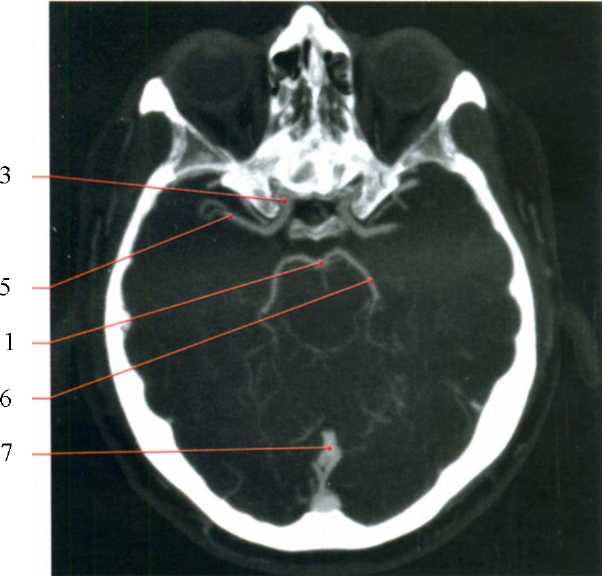

Сегменты сонной артерии кт

Сегменты сонной артерии кт 83 фото